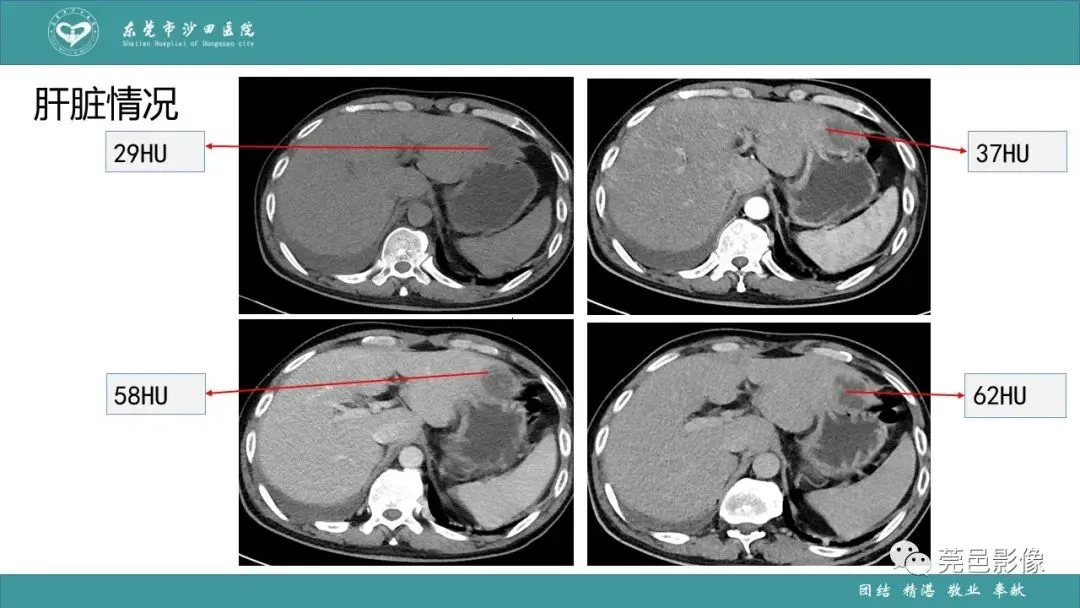

>课件 | 肺炎克雷伯杆菌肺炎影像学诊断与鉴别诊断

课件 | 肺炎克雷伯杆菌肺炎影像学诊断与鉴别诊断